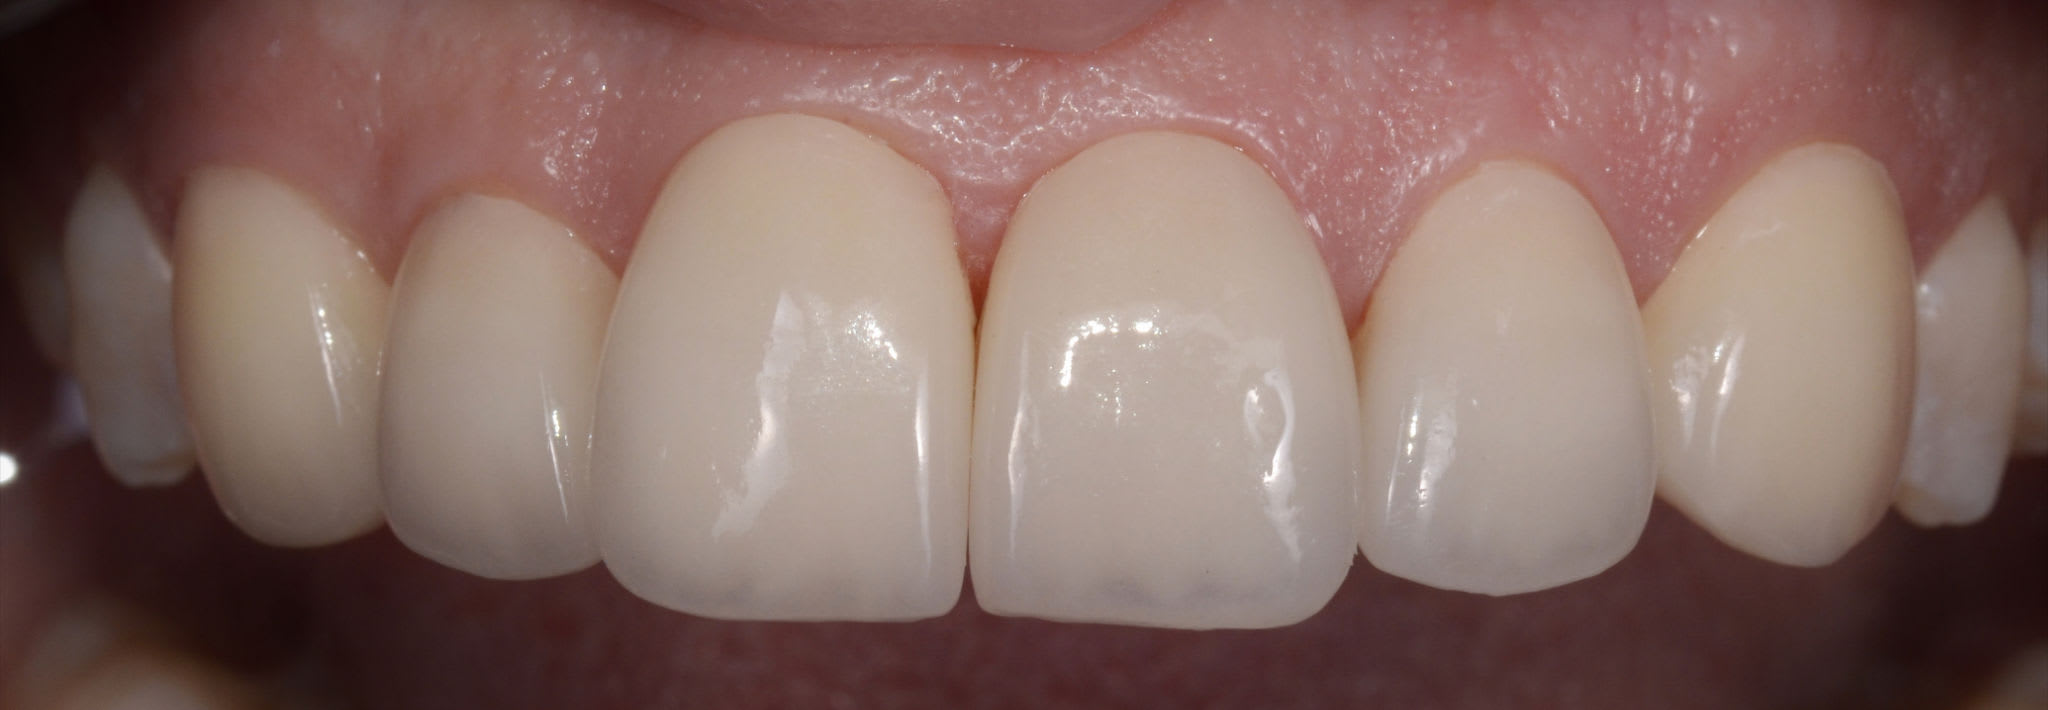

Bon les gars, y a rien là ?

(fait en 2012)

Alors, c'est pas de la déquichisation ça ?